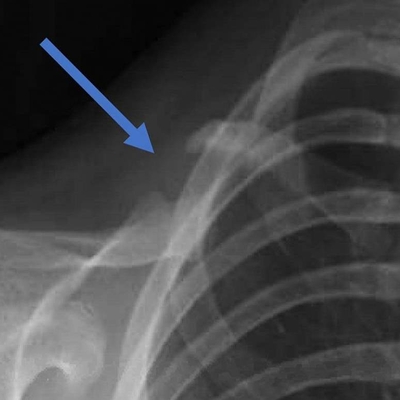

Click on an image below to view more info.